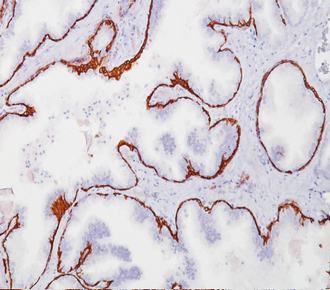

| 克隆号 : | OTI1C7 |

| Ig分类 : | IgG1 |

| 适用组织: | 冷冻/石蜡切片 |

| 阳性部位: | 细胞质 |

| 阳性对照: | 皮肤 |

| 特异性 : | 此抗体可以识别人的细胞角蛋白5和6,与CK4有微弱的交叉反应,与CK17、8、10、13、14、18和19无交叉反应。 |

| 推荐效价: | •原液使用前应以适当比例稀释 推荐稀释度为1:100~1:200 •工作液不必稀释,直接滴加使用 |